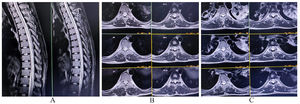

MRI showed mildly roomy CSF space around the dorsal cord without any signal changes in the cord suggestive of focal dorsal cord atrophy (Fig. 3A, B, C) with no abnormal findings in the brain. CSF evaluation was non-contributory. A complete blood cell count, renal, hepatic, and thyroid function tests, serum electrolytes, and blood glucose profile were within normal limits. Serum B12, folate, copper, and vitamin E levels were normal. Autoimmune and paraneoplastic panels were negative, including a whole-body 2-[fluorine 18] fluoro-2-deoxy-D-glucose positron emission tomography/computed tomography scan. Finally, a diagnosis of delayed toxic myeloneuropathy following organophosphate poisoning was made. He was put on intravenous bolus methylprednisolone (1 g/day for 5 days) followed by oral steroids in gradually tapering dosage over the next month along with vitamin D, calcium, and potassium supplements. His neurological condition remained static.